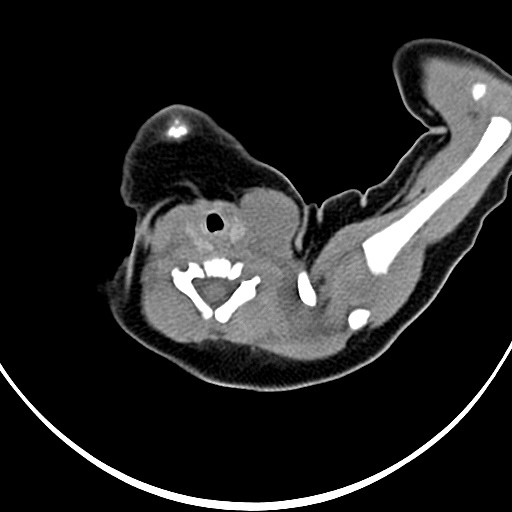

标题: PED1779:左侧锁骨下方异常密度影 请指教 [打印本页]

患者,男,1月,出生后一月,无明显诱因出现颈部左前方肿块。体检:左侧颈部轻度凸起包块,触之较硬。

病灶与左侧胸锁乳突肌分界不清,软组织密度,不似囊性改变,从病人的年龄及病变性状首先要除外先天性斜颈(肌性斜颈)可能。

左侧胸锁乳突肌肿大,考虑产伤所致

胸锁乳突肌挛缩(斜颈)?